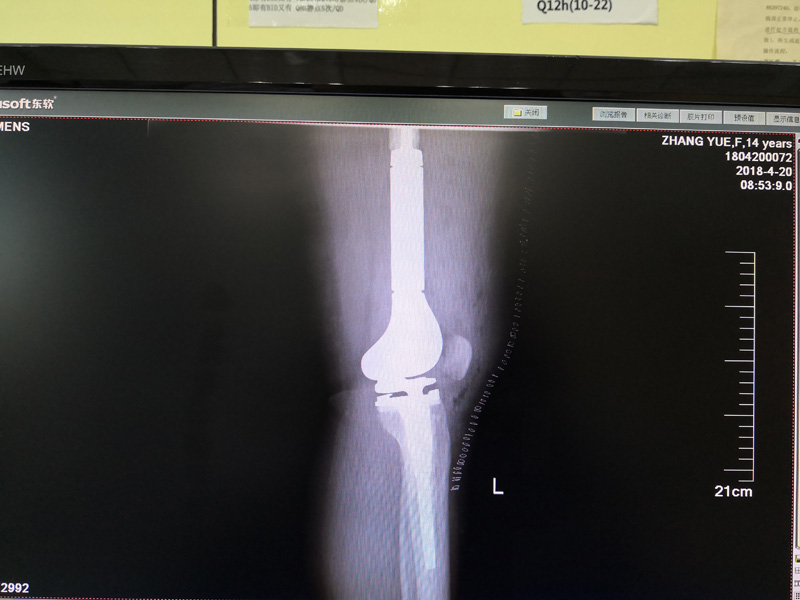

骨肉瘤手术手术后

患者张某,女,14岁,诊断为“左股骨远端骨肉瘤”,当地医院因为医疗技术和能力的限制,只能考虑截肢手术。患者家属通过平台推荐,指定到哈尔滨医科大学附属第二医院骨关节科找到陶树清主任就诊。经过严密、悉心的诊断,对小女孩还进行了“瘤段切除、肿瘤假体置换”手术,保留了小女孩肢体的健全,同时使她能够正常行走。

携生医疗骨肉瘤手术后X光片(正位)

骨肉瘤手术后X光片(正位)